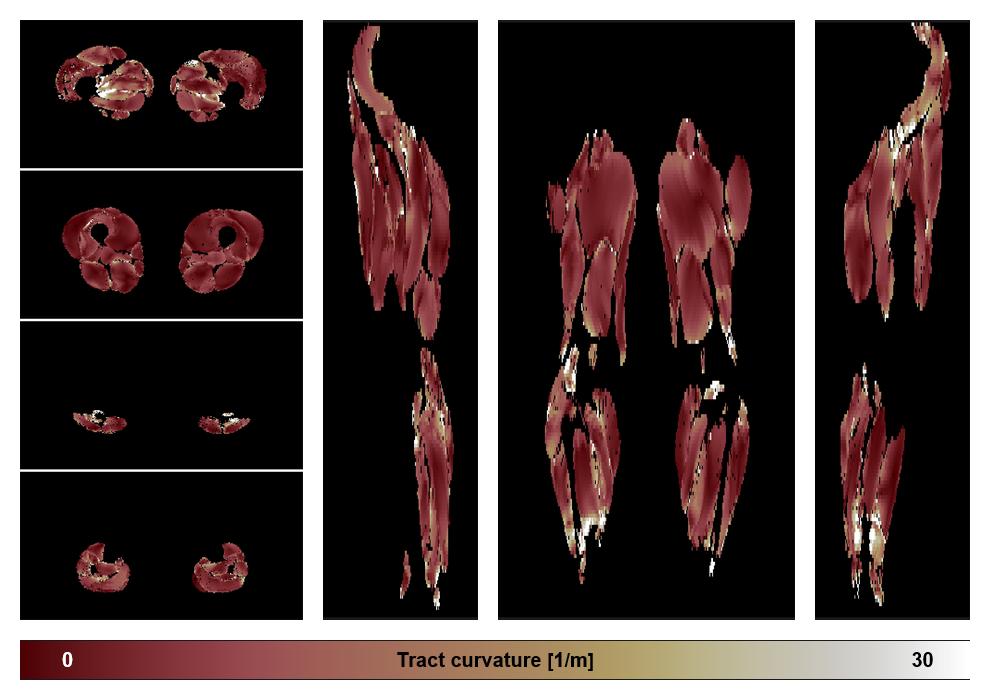

• Muscle fiber curvature map

Muscle fiber tract curvature map based on whole leg DTI based fiber tractography.